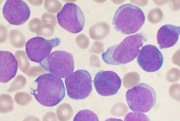

| 17:01, 27 בנובמבר 2017 | לוקמיה.jpg (קובץ) |  |

14 קילו־בייטים | דנה לוי | 1 | |